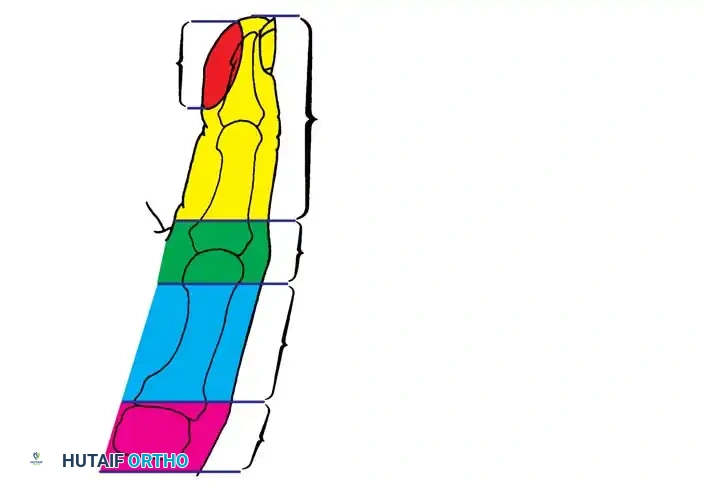

Levels of Amputation and Reconstructive Choice

- Distal to the IP Joint: Only appropriate soft-tissue coverage is necessary. If sensibility in the pinch area is grossly impaired, a neurovascular island transfer may be indicated.

- At the MCP Joint or Proximal Phalanx: The thenar muscles usually remain intact, stabilizing the digit. Deepening of the thumb web via Z-plasty or lengthening of the metacarpal by bone grafting (Gillies-Millard technique) is indicated.

- Proximal Metacarpal/CMC Joint: Requires complex reconstruction such as pollicization of the index finger or microvascular toe-to-hand transfer.